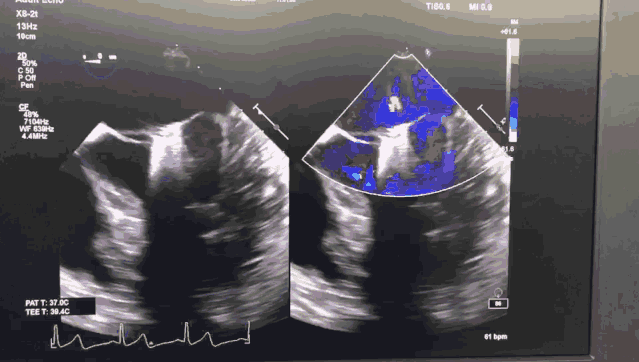

患者是71岁老年男性,体格消瘦,极重度二尖瓣反流,后叶P2及部分P3脱垂,同时合并重度肺动脉高压,STS评分6.1%,外科手术风险高。

今日手术转播的导管操作时间仅用8分钟,一次性成功。患者术后即刻效果满意,二尖瓣反流从极重度减少到轻中度,未出现二尖瓣狭窄,肺动脉高压从重度降为正常,手术效果良好。

图1 ValveClamp术前经食道心超

图2 ValveClamp术后经食道心超